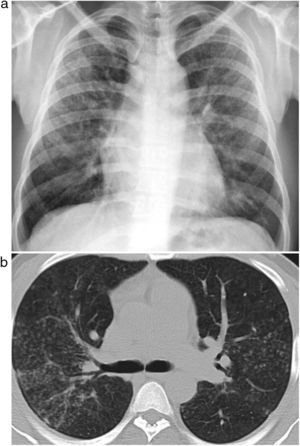

ResultsWe recruited 96 patients who met the inclusion criteria, all of whom were men with a mean age of 44 years (SD 8), ranging between 27 and 59 years. Patient provenance is shown in Table 1. Clinical presentation was distributed into 53 cases (55%) of simple silicosis and 43 (45%) of complicated silicosis. Ten patients met the criteria for accelerated silicosis. The average time of exposure to quartz conglomerates was 15 years, ranging from 5 to 34 years. In total, 77% of workers handled other rocks concurrently, mainly granite, and the average duration of total exposure to any material with silica content was 20 (SD 8) years. Eighty percent of the patients were still actively employed and exposed to the occupational risk at the time of diagnosis. A total of 77% of cases reported inadequate technical prevention measures and 74% did not use personal protective equipment. Patients with accelerated silicosis had an average age of 33 (SD 6) years, ranging from 27 to 44 years. Seven of these patients (70%) fulfilled the criteria for complicated silicosis, and 4 cases (40%) showed areas of ground glass opacities associated with interstitial nodules (Fig. 1).

Chest HRCT is well known to increase sensitivity in the detection of progressive massive fibrosis (PMF).32 Nodular pattern findings, subpleural involvement and lymphadenopathies are similar to those of classic silicosis,33 although the presence of ground glass patterns of moderate extension in 30% of patients in our series should be noted, in addition to the existence of the usual nodules (Fig. 1). Several of the cases described by the Australian and Italian authors10,23 were significant for the presence of lymphocytosis in bronchoalveolar lavage, findings not described in classic silicosis. All this suggests a different form of the disease, probably more disseminated and aggressive than usual, which can develop more rapidly to an irreversible, fibrosing process. In our series, 10 patients met the criteria for accelerated silicosis.34 This group is too small to draw meaningful conclusions, but a profile is emerging of young people employed in cutting and polishing stone with increased use of conglomerates, who develop PMF (Fig. 2) and a tendency to lower lung function values. The histological and mineralogical study of samples obtained by transbronchial cryobiopsy35 helped exclude sarcoidosis in young people who showed a short latency period from the start of exposure (Fig. 3), and in other cases it revealed patterns of usual interstitial pneumonia associated with the deposit of silica particles (Fig. 4),36,37 which introduces therapeutic prospects not yet addressed in this disease.38